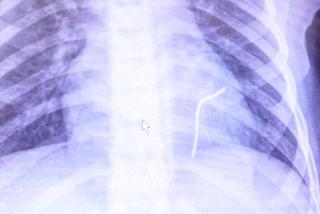

Pięciocentymetrowy kawałek metalowego drutu wystrzelił spod ostrza kosiarki jak z procy, przeszedł przez klatkę piersiową stojącego kilka metrów obok Przemka (5 l.) z okolic Opoczna (woj. łódzkie) i utkwił w jego sercu. Gdyby przebił je na wylot, chłopiec wykrwawiłby się na śmierć - Miał mnóstwo szczęścia – mówią lekarze z łódzkiego szpitala Centrum Zdrowia Matki Polki, którzy usuwali ciało obce z jego organizmu.

Stan chłopczyka błyskawicznie się pogarszał. Karetka przewiozła go do szpitala w Opocznie, gdzie lekarze ustalili, że w jego serduszku tkwi metalowy przedmiot. Zaczęła się dramatyczna walka z czasem, bo liczyła się każda minuta. Helikopterem Lotniczego Pogotowia Ratunkowego przetransportowano Przemka do specjalistycznego szpitala Centrum Zdrowia Matki Polki. Tu natychmiast trafił na blok operacyjny.

- Zabieg trwał około półtorej godziny – mówi Marek Kopala, ordynator Kliniki Kardiochirurgii. - Nie był specjalnie skomplikowany, natomiast chłopiec miał dużo szczęścia. Okazało się, że drut wbił się w serce i tam się zatrzymał. Gdyby przeleciał na wylot, najprawdopodobniej doszłoby do wykrwawienia i tego mógłby nie przeżyć.